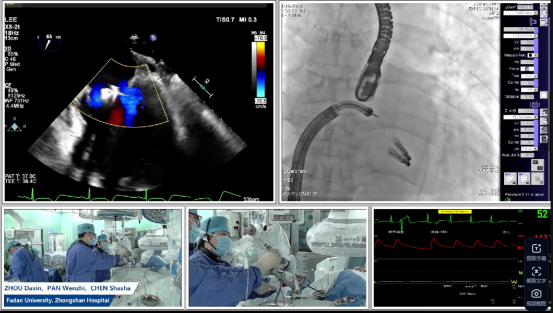

潘文志教授、陈莎莎教授、李伟教授共同协作,在手术直播中完整展现TEER的精准操作:术中房间隔穿刺高度4.0cm,为器械送达创造最优路径;针对后叶栓系严重的问题,手术团队运用DragonFly™二尖瓣夹的独立捕获功能,尽可能捕获充足瓣叶以限制脱垂运动,同时将夹合角度保持在20°,在瓣叶张力与反流改善之间达成最佳平衡后,成功释放第一枚XW0612(长宽)夹子,即时评估显示M侧无残余脱垂及反流;随后手术团队快速在L侧植入第二枚XN0412(长窄)夹子处理残余反流,全程操作流畅高效。术后即刻超声验证显示该患者二尖瓣反流完全消失,跨瓣压差仅3mmHg,肺静脉逆流现象彻底消除,手术达到超预期效果。

现场与会专家指出:“整个手术过程中,复旦大学附属中山医院手术团队的操作展现出极高的精准性与娴熟度——从术前规划到术中实时调整,每一步都体现了深厚的经验积累与技术水平;从超声影像中可以看到,无论是释放前还是释放后,二尖瓣夹性能始终保持稳定,操作流畅连贯。尤其令人印象深刻的是在第二个夹子植入时,潘文志教授从进入系统到夹合完成,全程仅用时五分钟,迅速而精准地将夹子以完美的肩并肩状态紧贴首枚夹子完成置入。整个流程高效、稳定,充分体现中国团队在TEER技术上的高超水准。”在场专家连连称赞“amazing”,对潘文志教授娴熟而完美的操作表示赞叹。“我们对手术效果和团队的专业能力表示充分肯定,也期待在长期随访中,患者临床症状能获得进一步改善。”